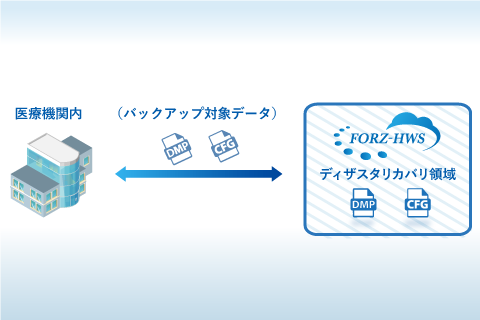

装置共同利用サービス データバックアップサービス

データバックアップサービス 画像ファインリングシステム PACS

健診システム FORZ-HWS(クラウドサービスシステム)

FORZ-HWS(クラウドサービスシステム)